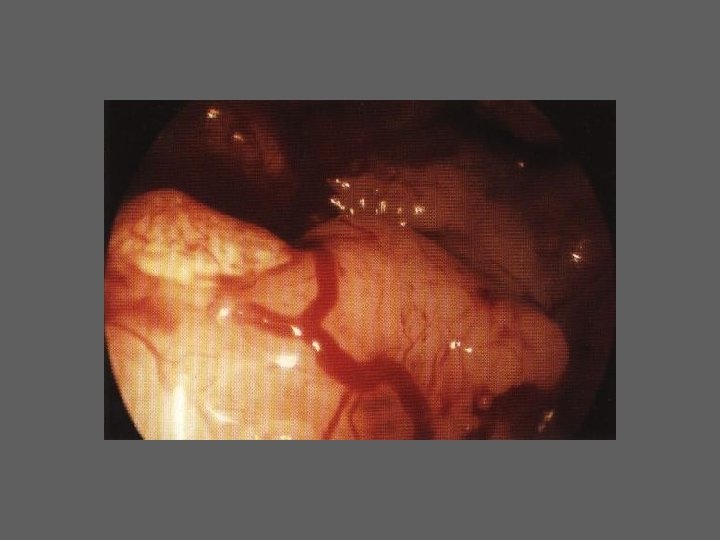

HISTEROSCOPIA DIAGNÓSTICA • Indicações /Importância (6 grupos) I. Esclarecimento de determinados sintomas ou de situações ginecológicas particulares II. Infertilidade III. Oncologia IV. Antecedentes de complicações Obstétricas específicas V. Esclarecimento de resultados “anormais” de outros meios de diagnóstico VI. Avaliação pré e pós-operatória da cirurgia histeroscópica

HISTEROSCOPIA - INDICAÇÕES Todas a situações em que se julgue vantajosa uma visualização completa da cavidade uterina, em particular: – Metrorragias – Dismenorreia adquirida – Infertilidade – Abortamentos de repetição e parto pré-termo – HSG anormal – DIU “perdido” – GIFT e ZIFT – Tratamento cirúrgico da patologia intracavitária: ● pólipos, miomas, septos, sinéquias, recessões endometriais ● baixos custos, reduzida morbilidade